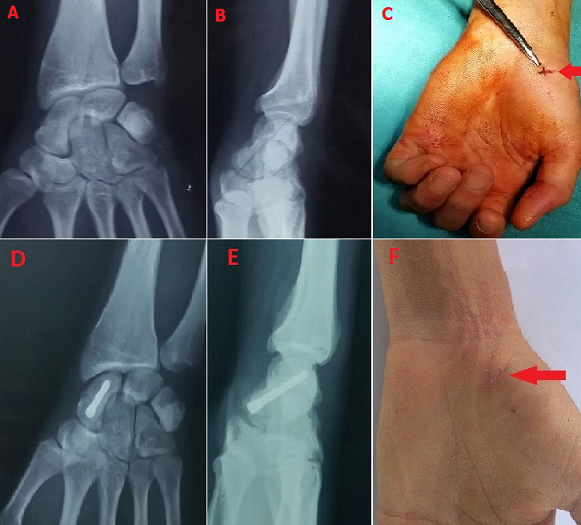

En plus des bénéfices de la chirurgie à ciel ouvert du scaphoïde, la réduction de la durée d'immobilisation et le retour rapide au travail, le vissage percutané permet également de réduire le risque opératoire et d'éviter un délabrement des tissus mous, une dévascularisation du foyer de fracture et par conséquent cette technique présente moins de risque de pseudarthrose. Les auteurs rapportent le cas d'un patient de 27 ans, opéré pour une fracture non déplacée type 4 de Schernbereg. Il a bénéficié d'un vissage percutané rétrograde. Les suites étaient simples, et la sortie à J1 post-opératoire avec une orthèse du poignet, que le patient à garder pendant 15 j, puis il a commencé l'auto rééducation. La consolidation a été obtenue vers 2 mois et 15j, il s'agit d'un étudiant qui n'as pas arrêté ses cours. Cependant, on lui a interdit tout travail en force pendant 3 mois. Il s'agit d'une technique qui donne de très bon résultats dans l'immédiat, son indication est limité aux fractures non déplacées du scaphoïde.